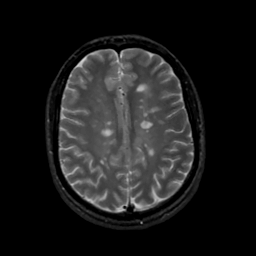

MR Study #16, June 23, 1991 -- Slice #34

[Home][Help][Clinical][Tour 1][Tour 2] Slice 34